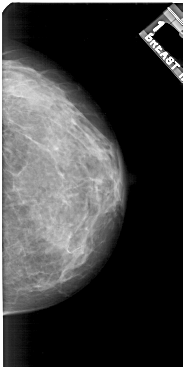

ics_version 1.0 filename A-1921-1 DATE_OF_STUDY 7 6 1994 PATIENT_AGE 36 FILM FILM_TYPE REGULAR DENSITY 4 DATE_DIGITIZED 22 6 1999 DIGITIZER HOWTEK 43.5 SEQUENCE LEFT_CC LINES 5011 PIXELS_PER_LINE 2851 BITS_PER_PIXEL 12 RESOLUTION 43.5 OVERLAY LEFT_MLO LINES 5371 PIXELS_PER_LINE 3076 BITS_PER_PIXEL 12 RESOLUTION 43.5 OVERLAY RIGHT_CC LINES 5131 PIXELS_PER_LINE 2551 BITS_PER_PIXEL 12 RESOLUTION 43.5 NON_OVERLAY RIGHT_MLO LINES 5461 PIXELS_PER_LINE 2626 BITS_PER_PIXEL 12 RESOLUTION 43.5 NON_OVERLAY |